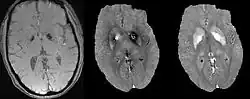

Differentiation between calcification and iron. From left to right are magnitude, phase and QSM.

It has been confirmed in in vivo and phantom experiments that cortical bones, whose major composition is calcification, are diamagnetic compared to water.[11][18] Therefore, it is possible to use this diamagnetism to differentiate calcifications from iron deposits that usually demonstrate strong paramagnetism.[19] This may allow QSM to serve as a problem solving tool for the diagnosis of confounding hypointense findings on T2* weighted images.